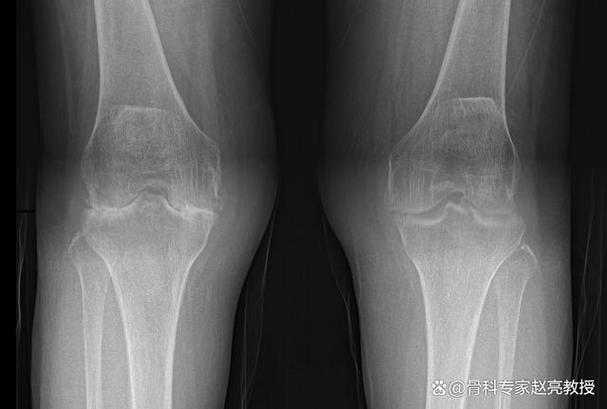

中晚期类风湿关节炎(X光片可以看到典型改变)

随着病情发展,持续的炎症会侵蚀骨骼和软骨,这些在X光片上就清晰可见了,医生寻找的典型X光征象包括:

- 骨侵蚀:这是类风湿关节炎最具特征性的改变,表现为关节边缘、骨突部位出现虫蛀样、小洞样的骨质破坏,这是诊断的重要依据。

- 关节间隙狭窄:由于软骨被炎症破坏,骨头与骨头之间的距离会变窄。

- 关节畸形:如手指的“天鹅颈”样畸形、“钮扣花”样畸形,手腕的尺偏畸形等。

- 骨质疏松:关节周围的骨骼会变得疏松、密度降低。

- 关节脱位/半脱位:严重的骨质破坏和韧带松弛会导致关节位置改变。